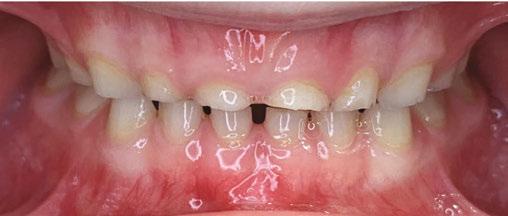

The following procedures were accomplished under general anesthesia on an outpatient basis — full mouth dental radiographs and a comprehensive oral exam. A complex odontoma was found to be the etiology of the noneruption of the maxillary right permanent central incisor (Figure 2). Since dental caries also was diagnosed, a full-mouth prophylaxis was completed. Dental caries was controlled, and teeth were restored. A 5 mm incision was made on the gingiva over the impacted maxillary right permanent central incisor, and two tooth-like structures were extracted from the right maxillary incisor area. A postoperative periapical radiograph was taken to confirm complete odontoma removal (Figure 3). Three interrupted sutures using 3-O chromic gut were placed.

At the postoperative consultation with the mother, we told her the tooth’s complete root formation might prevent its eruption. Orthodontic extrusion of the incisor was ruled out due to his behavior. A conservative approach with observation only was elected as treatment modality. This patient returned for follow-up appointments at ages 10, 11, 12, and 13. During all these visits, the maxillary right permanent central incisor had not erupted. At age 14, due to recurrent dental caries, the patient was taken to the local children’s hospital for dental rehabilitation again. During this second hospitalization, we noticed that the right maxillary central incisor was partially erupted into the oral cavity (Figure 4).

Figures 2 and 3: 2. Periapical radiograph of involved area taken in the operatory during initial dental rehabilitation under general anesthesia (left). 3. Periapical radiograph of involved area taken in the operatory during initial dental rehabilitation under general anesthesia immediately after odontoma removal (right)

Figure 4: Photograph of area at 14 years old during second rehabilitation under general anesthesia